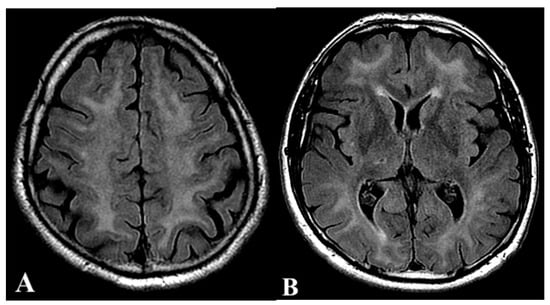

2.1. First Case